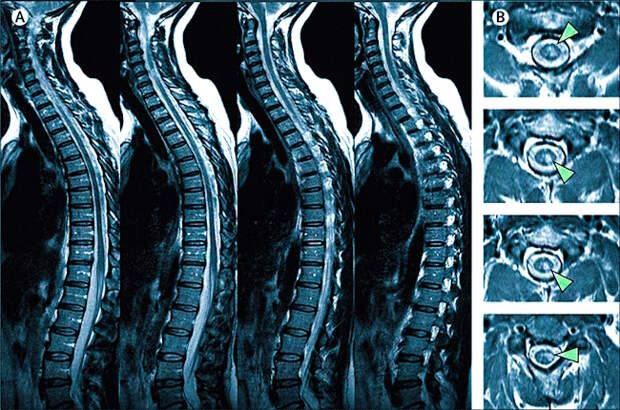

Магнитно-резонансная томография является высокоинформативным методом диагностики различных заболеваний позвоночного столба. Она позволяет визуализировать состояние позвонков, межпозвонковых дисков, спинного мозга и окружающих мягких тканей.